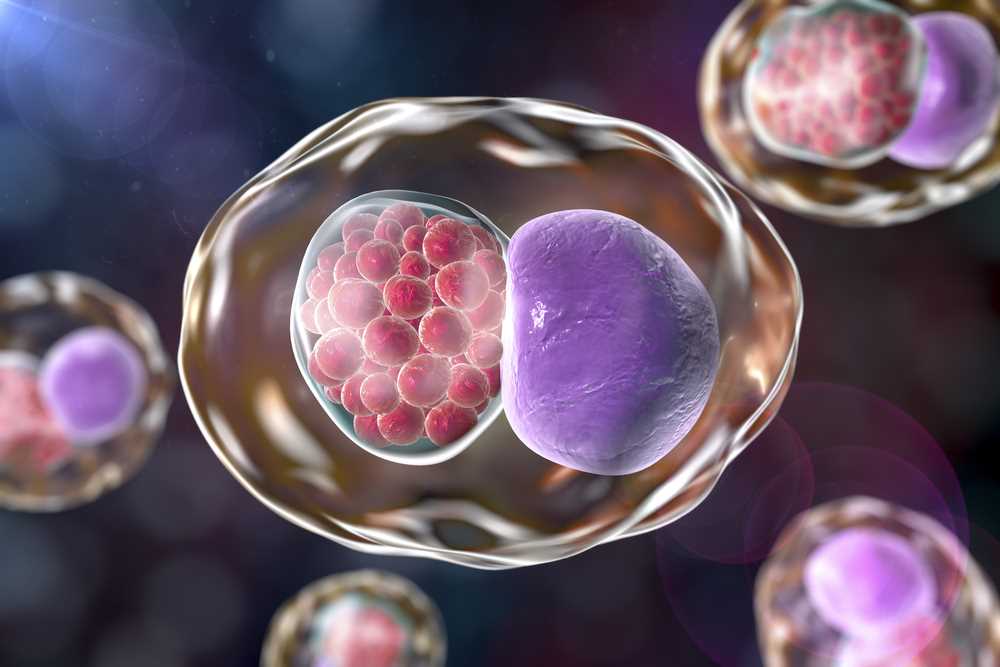

Chlamydie jsou častou infekcí, která může postihnout různé části těla, včetně plic. Tyto bakterie se šíří zejména přímým kontaktem s infikovanou osobou nebo prostřednictvím nechráněného sexuálního styku. Infekce chlamydiemi na plicích může způsobit různé příznaky a může být obtížné ji diagnostikovat.

Co jsou to chlamydie a jaké jsou příznaky této infekce?

Chlamydie jsou bakterie, které se mohou vyskytovat v různých částech těla, včetně plic. Příznaky chlamydiální infekce plic mohou zahrnovat kašel, horečku, bolest na hrudi a dušnost.